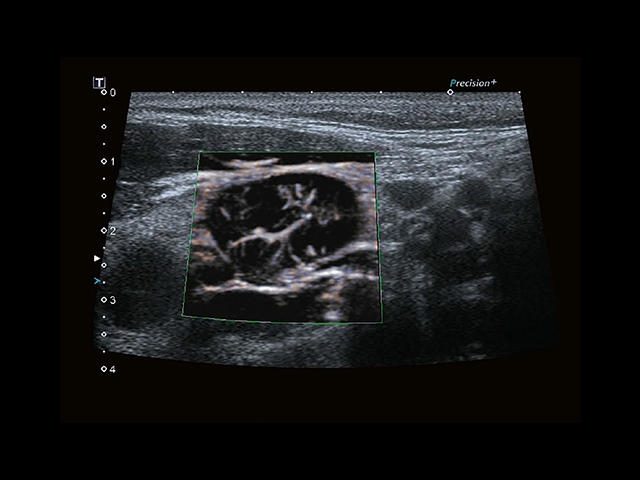

Обновленная версия легендарного УЗ-сканера. Стационарный аппарат экспертного класса Aplio 500 Toshiba NEW, визуализирует анатомические структуры в высоком разрешении. Модель позволяет выявить микрокальцификаты, новообразования, нарушения в работе сердца, сосудов и мышц. Присутствует функция виртуальной эндоскопии, 4D-сканирования, эластометрии тканей, УЗИ с контрастированием. За повышение качества изображения отвечают технологии ApliPure и Superb Microvascular Imaging. Первая задействует возможности пространственного и частотного кодирования, формирует цельный визуальный ряд с сохранением клинических маркеров. Вторая улучшает отображение микрососудистого русла, используя доплеровский эффект. Модель оснащена 21-дюймовым монитором, имеет 4 активных порта. Возможно подключение педиатрических, интраоперационных, лапароскопических и чреспищеводных датчиков.

• MicroPure. Высокотехнологичное решение в области выявления микрокальцификатов – маркеров новообразований злокачественного типа. Маркеры идентифицируются путем изучения затененных изображений целевого участка. Микрокальцификаты отображаются в виде белых пятен.